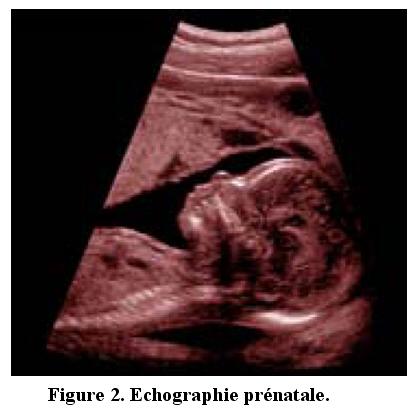

Les applications des ondes acoustiques sont multiples et diverses : échographie et communication sous-marine, contrôle non destructif des pièces opaques, échographie médicale, imagerie sub-surfacique de circuits électroniques, dispositifs tactiles.

Deux applications seront présentées lors de la conférence. La première concerne l'imagerie médicale où le principe de l'échographie est présenté dans un premier temps et suivi d'une démonstration avec un système commercial. La deuxième application concerne les dispositifs tactiles où on montrera qu'avec un couple de capteurs il est possible de rendre n'importe quel objet rigide sensible au toucher en imageant simplement sa surface.